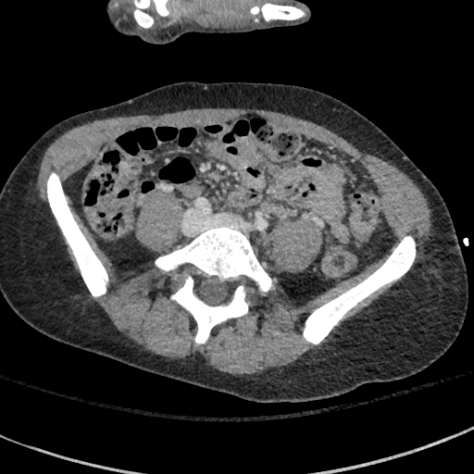

Fig. 3 visualizes sample abdominal CT images with varying quality levels from the test set. The predicted IQA scores show strong agreement with the reference scores across different noise and artifact intensities, which indicates the robustness of CAP-IQA in accurately quantifying CT image quality. The kernel density plot in Fig. 4 illustrates how prediction residuals are distributed across different IQA score groups. All curves are centered near zero, indicating balanced predictions without systematic bias toward any specific quality range. Moreover, the box plot presents the distribution of absolute prediction errors across different IQA score groups. The median errors remain low and consistent, showing that CAP-IQA performs reliably across all quality levels, with minimal variations and stability in predictions. Consistent with this interpretation, our pairwise testing using the Kruskal-Wallis H-test further confirms that there is no significant difference in performance for different IQA score groups (p-value 0.38).

4.8 Real Clinical Evaluation

We also evaluated the proposed CAP-IQA model on an in-house dataset. Fig. 8 displays sample images from the dataset. We retrospectively collected real clinical CT images from the University of Kentucky Medical Center with approval from the Institutional Review Board. A total of 91,514 image slices from 336 pediatric patients aged 2-12 years were used for testing the generalizability of CAP-IQA. Since these images have already been used for clinical diagnosis, they are expected to be of high quality (>3, as per the IQA scoring criteria in Table 1). Slice-wise IQA scores predicted by the model were averaged to obtain the overall score for each of the CT scans. The average IQA score across the 336 pediatric scans is 3.8582, with a correlation of variation of 2.1447. As seen in Fig. 9, the predicted scores are tightly grouped around the mean, with scores above the diagnostic-quality threshold of 3. The relatively high predicted scores align with expert radiologists’ assessments, indicating that the scans retain good diagnostic quality. Overall, the results demonstrate that CAP-IQA performs reliably in real-world clinical settings, and the model consistently and accurately assesses quality across diverse patient data.

![]() |

| 3.95 | 3.71 | 3.94 |

| 3.46 | 3.79 | 3.55 |